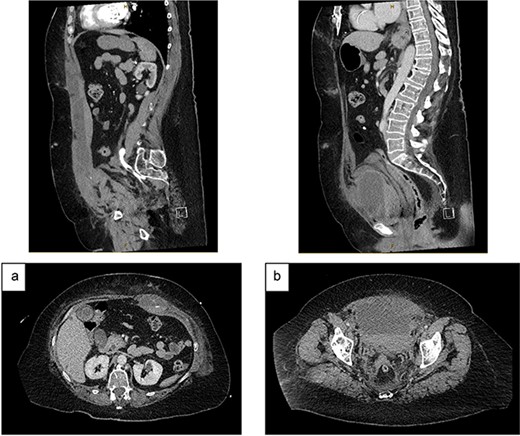

On examination, she was haemodynamically stable and afebrile. She had a soft abdomen, widespread abdominal bruising, and significant tenderness to the left of her umbilicus, without a discrete palpable mass. Urinalysis showed a trace of leucocytes but no blood or nitrites. Her blood tests showed haemoglobin 94 g/L, international normalised ratio 1.9, creatinine 63 μmol/L and estimated glomerular filtration rate (eGFR) >90 mL/min/1.73m2. A CT abdomen showed a left-sided RSH (62x38x131mm), with high-attenuating foci superiorly and inferiorly (Fig. 1). She was admitted to the Acute Surgical Unit and warfarin was withheld but therapeutic enoxaparin was continued on the advice of the Haematology team.

Contrast CT abdomen and pelvis (portal venous phase) demonstrating a left-sided RSH with active extravasation: (a) Sagittal view; (b) Axial view.